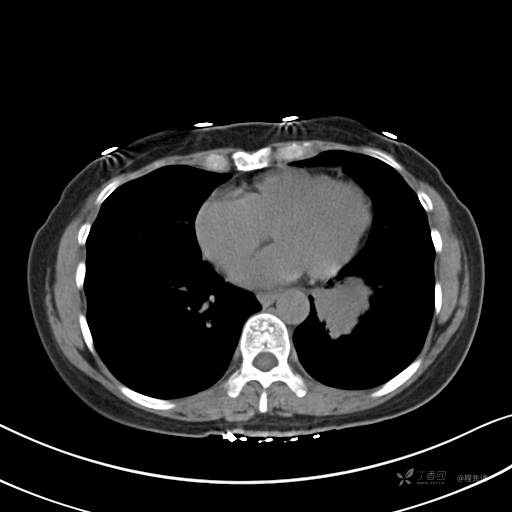

增强静脉期

静脉期CT值约84HU